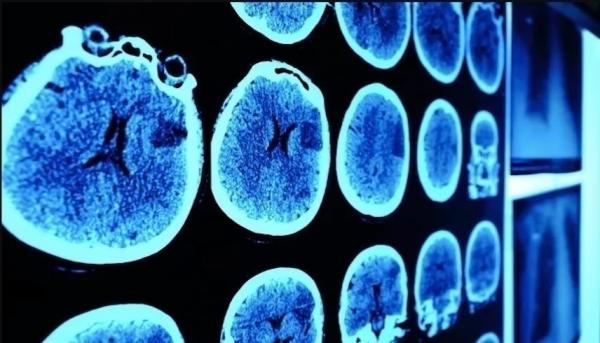

شخّص الأطباء إصابة الطفل لوكاس بسرطان الورم الدبقي، وهو نوع نادر من أورام الدماغ السرطانية، وهو في السادسة من عمره، وأخبروا والديه بأن فرص الشفاء لديه معدومة، وأنه لن يعيش طويلاً.

وبعد 7 سنوات من التشخيص، شفي الطفل الذي يبلغ عمره الآن 13 عاماً، تماماً من الورم، وأصبح أول طفل في العالم يشفى من الورم الدبقي في جذع الدماغ، والذي يعتبر سرطاناً فتاكاً.

ومنذ بداية العلاج، استجاب لوكاس بقوة لعقار “إيفيروليموس”، الذي تم وصفه له بشكل عشوائي، وبعد تلقي العلاج لعدة أعوام، أظهرت فحوصات التصوير بالرنين المغناطيسي، أن الورم اختفى بشكل كامل.